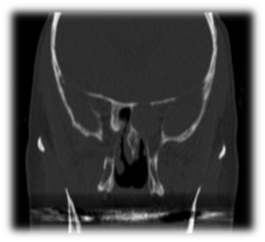

Allergic Fungal Rhinosinusitis AFS: Allergic fungal sinusitis is a non-invasive fungal sinusitis occurs in immunocompetent individuals in whom there is a strong inflammatory response to the fungal infection. This commonly results in a thick mucin that can be expansile and cause bony decalcification. There is also marked mucosal thickening and bone resorption due to the secretion of enzymes. Endoscopic examinations of these patients show the presence of allergic mucin and polyps. Major criteria for diagnosis by Bent and Kuhn their diagnostic criteria depend on the histologic, radiographic, and immunologic characteristics of the disease which include type 1 hypersensitivity, the presence of nasal polyposis, characteristic CT findings of heterogeneous hyperdensities that are often unilateral and asymmetric (Figure 3), an eosinophilic mucin and positive fungal stain or culture.16 AFS in sphenoid sinus can easily compress the cranial nerves. It was reported that cranial neuropathies develop in 10% of the sphenoid AFS with bone erosion. Treatment involves endoscopic sphenoidotomy to clear polyps and allergic mucin (Figure 4), and to restore the ventilation and drainage of sinuses with combination of medical therapy with corticosteroids. Anti-fungal treatment is usually not required. Histopathology is important to be obtained for the specimen which shows allergic mucin containing fungal components without any tissue invasion. These patients may get benefit from Immunotherapy post-op.

Figure 3 CT scan of bilateral sphenoid allergic fungal sinusitis./p>